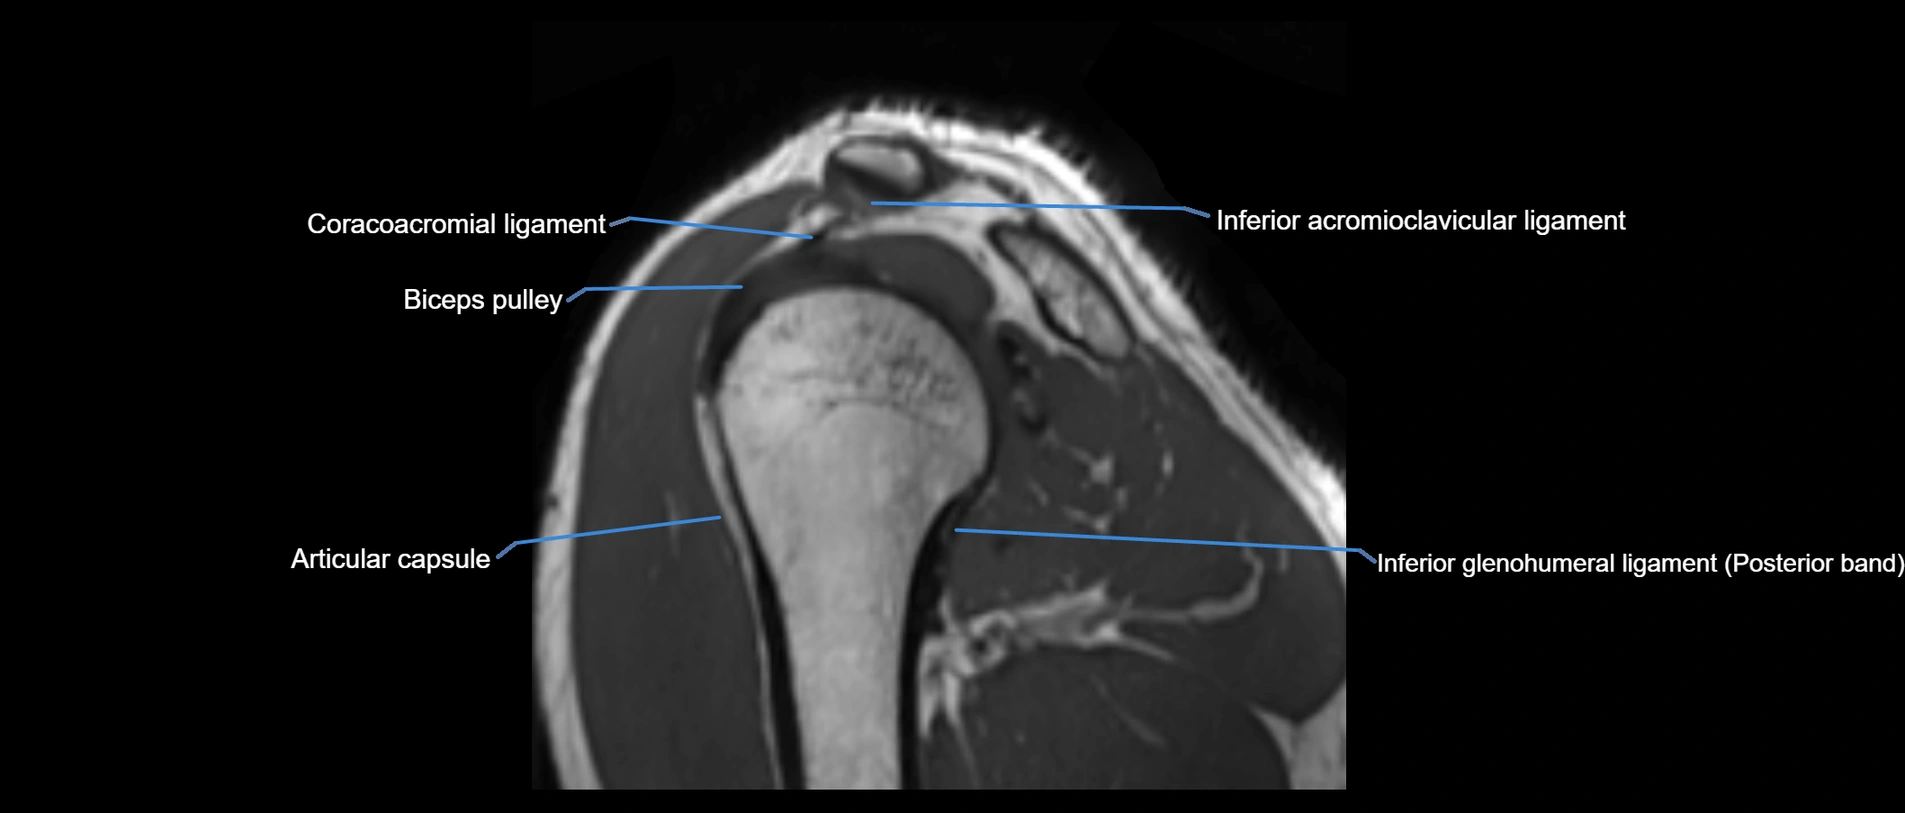

MRI images

image

MRI Appearance

• T1-weighted images:

• Normal ligament: Low signal (dark linear band) spanning acromion to clavicle.

• Surrounding fat planes: Bright, delineating the ligament clearly.

• Marrow of clavicle and acromion: Bright due to fatty content.

• Tears: Discontinuity or irregular thickening with intermediate-to-bright signal.

• Chronic injury: Thinning, fraying, or irregular low-signal fibers with adjacent scarring.

• T2-weighted images:

• Normal ligament: Low signal, homogeneous.

• Partial tear or sprain: Focal hyperintensity or thickening.

• Complete tear: Discontinuity with fluid-bright gap between clavicle and acromion.

• Associated edema: Bright signal in distal clavicle or acromion marrow.